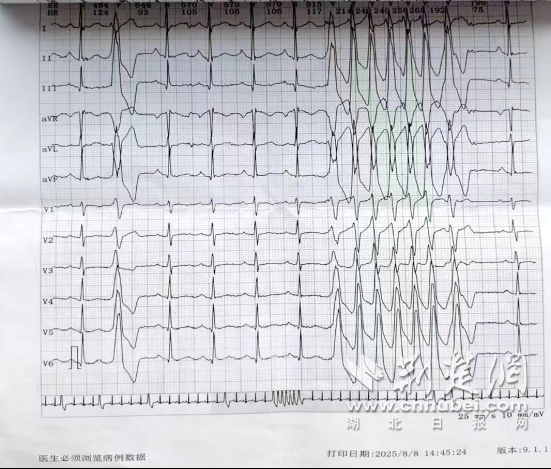

- 十堰市中西医结合医院胸脑外科团队精准介入治疗成功挽救危重患者生命